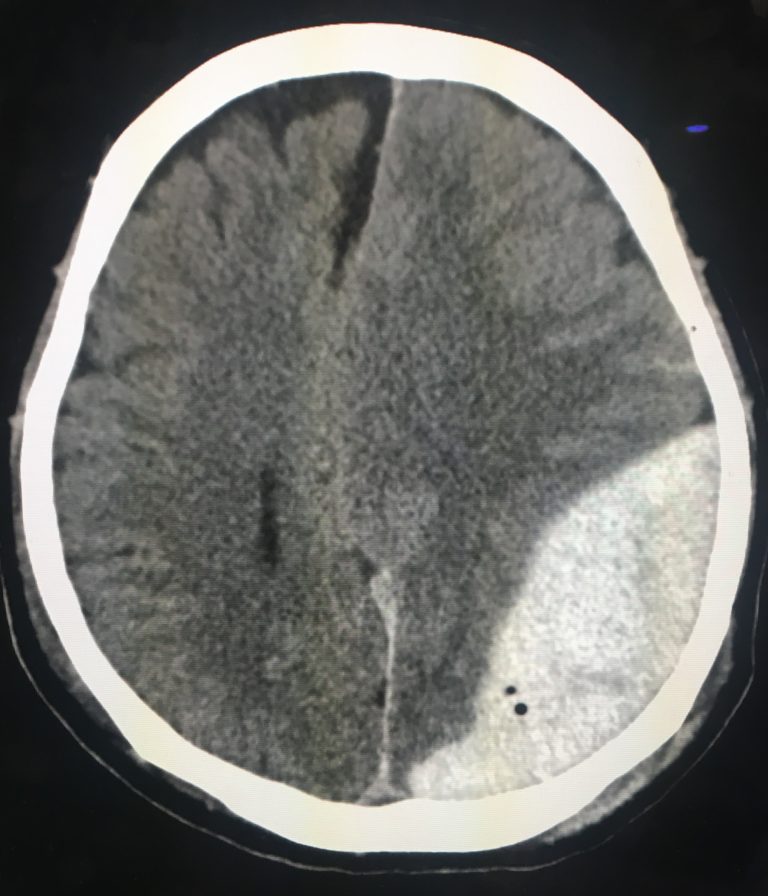

頭部CTにより、血腫をレンズ状の高吸収域としてみとめ、圧排のためにミッドラインシフトがみられる。